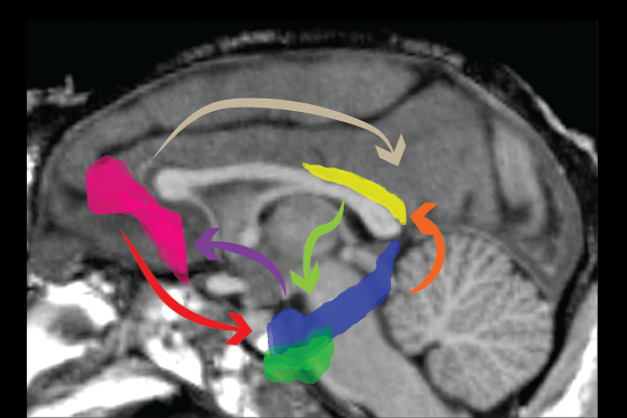

我们使用猕猴作为动物模型来研究上述问题,旨在了解相互连接的多脑区网络的神经活动如何支持记忆和行为。以大脑海马区为中心,研究与其相连脑区(包括压后皮层、顶叶皮层、眶额皮层、扣带回等)。结合使用自然状态下的动物行为、精确的三维运动捕捉和无线眼动追踪、大规模无线神经电生理技术和因果神经调控技术。同时我们使用基于触屏和虚拟现实的实验任务来探究记忆编码和巩固,及空间导向的神经基础。